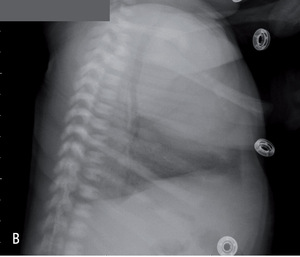

Rycina 2. Zdjęcia przeglądowe tylno-przednie (A) i boczne (B) dwutygodniowej dziewczynki z sekwestracją zewnątrzpłatową lewego płuca.